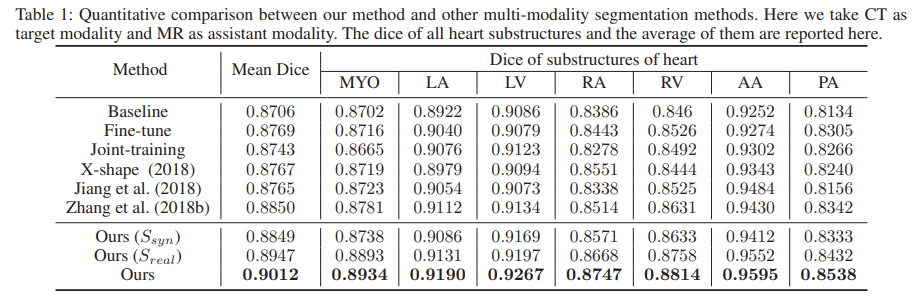

본 논문에서는 자신들의 학습 기법의 효과를 보이기 위해 Baseline으로 단일 CT 데이터만을 사용해서 학습한 모델을 선정하였습니다. 그리고 Ours 성능의 경우 3가지가 있는것을 볼 수 있는데 제일 아래 row의 세번째 성능은 두 Segmentation 모델의 예측을 합친 성능입니다.

성능의 경우 7개의 class (좌심실 혈강(LV), 우심실 혈강(RV), 좌심방 혈강(LA), 우심방 혈강(RA), 좌심실 심근(MYO), 상행 대동맥(AA), 폐동맥(PA) ) 에 대한 각 성능과, 이들의 평균인 Mean Dice 를 나타낸 것입니다.

2. 두 모델 S_real과 S_syn 은 CT 도메인의 이미지를 학습때 봤기 때문에 test 시에도 CT 도메인의 이미지를 입력으로 받을 수 있습니다. Ours(S_real)과 Ours(S_syn)은 입력 CT 이미지를 각 모델에 통과시킨것을 의미하고, 최종적인 Ours는 입력 이미지를 두 모델에 모두 통과시킨 뒤 ensemble 방식으로 합친 것이라고 합니다. 합치는 과정에 대한 구체적인 설명 없이 그냥 ‘ensemble로 두 예측을 합쳤다’ 라고 표기되 어 있네요.. gt와 비교해서 정답으로 인정하는건 아마 아닐듯합니다. 평가지표의 경우 loss에 적용된 Dice 지표가 사용되는데, 7개 각 클래스에 대한 Dice를 계산하고 이들의 평균(Mean Dice) 치를 사용하게 됩니다.

3. Joint-training과 fine-tune 방식은 하나의 seg 모델을 사용하는 공통점이 있긴 하다만, Joint-training의 경우는 CT와 MRI 이미지를 한꺼번에 학습시키는 방식이고 fine-tune 방식은 MRI 데이터로 학습을 시킨 뒤 target인 CT 데이터로 fine tuning을 하는 방식입니다. Ours(sync), Ours(real)는 2번에서 설명 드리긴 했지만, 이해하신 내용이 맞습니다. 본 논문의 기법으로 학습 시킨 뒤 각 stream별로 예측을 수행한 결과입니다.